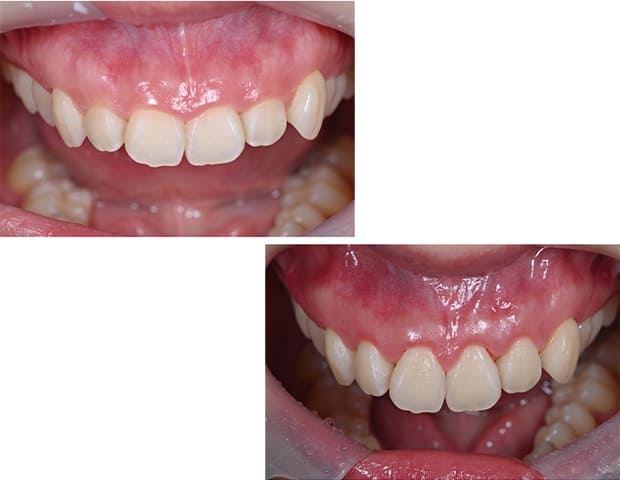

Case01

-

- 原因

- ガミースマイル

- 治療回数

- 1回

- 治療期間

- 術後治癒も含めて約1か月

- 治療内容

- ガミースマイル改善治療

- 治療費用

- 121,000円

(1ブロックあたり、6前歯部分)

笑った時に歯茎が見えてしまうガミースマイルを改善したいとのことでご来院された患者様です。術後も大変満足していただきました。